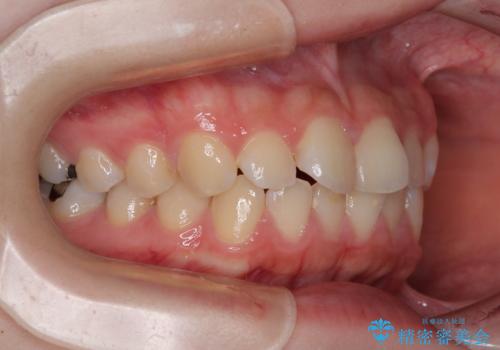

- 上下前歯部のデコボコを気にして来院された患者様です。

叢生は軽度であったため、マウスピースでもワイヤー装置でも対応可能でしたが、マウスピースを長時間使用する自信がないとのことでワイヤー装置にて矯正治療を行うこととしました。

叢生が軽度であったため、僅か半年で装置を除去することができました。